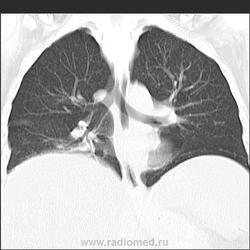

Прозрачность обеих легких равномерно неинтенсивно снижена за счет наличия множественных, плохо дифференцируемых мелкоочаговых теней, сливающихся между собой и расположенных главным образом во внутренних отделах легких, ближе к корням легких, образуя картину «бабочки». Сосудистый рисунок диффузно усилен, в виде радиальных извитых теней за счет перибронхиальной и периваскулярной инфильтрации. Линейные тени пластинчатых ателектазов. Корни легких малоструктурны. Органы средостения не смещены. Сердечная тень не увеличена."

Я не вижу "Бабочку", а Вы?

Из-за почечной недостаточности контрастирования не будет. Такая картина в легких мне впервые попадается. Есть несколько вариантов, но очень хочется услышать мнения коллег! Какие будут мысли?

Михаил Анатольевич, это всё замечательно, то есть наоборот для пациента. Вопрос: как гипо- и авитамоноз В1 проявляются в данном случае в легочном рисунке? Пряник не жалко: ЧТО С ЛЕГКИМИ???

В легких - рентгенограмму я описала как усиление за счет интерстициального компонента. Корень кажется обрубленным: из-за асцита высоко стоит диафрагма, нижние отделы легких поджаты. Пневмосклероза я не вижу. А по КТ не знаю, как интерпретировать: интерстициальный отек, токсический васкулит?

Михаил Анатольевич, Ваши комменты нельзя использовать в протоколе рентгенологического исследования . Что посоветуете писать РЕНТГЕНОЛОГУ при описании подобной рентгенограммы? Норму? Отек легких? Гиповитаминоз и гипоальбуминемию я не могу написать в протоколе, это ясно клиницисту и без меня...

Тогда, учитывая всё вышесказанное, вероятно интерстициальный отёк ( гипопротеинемия, почечная недостаточность, токсическое поражение...)

Парочка моих шаблонов, наверное первый соответствует настоящему состояниюПрозрачность обеих легких равномерно неинтенсивно снижена за счет наличия множественных, плохо дифференцируемых мелкоочаговых теней, сливающихся между собой и расположенных главным образом во внутренних отделах легких, ближе к корням легких, образуя картину «бабочки». Сосудистый рисунок диффузно усилен, в виде радиальных извитых теней за счет перибронхиальной и периваскулярной инфильтрации. Линейные тени пластинчатых ателектазов. Корни легких малоструктурны. Органы средостения не смещены. Сердечная тень не увеличена.

Прозрачность обеих легких неравномерно, преимущественно в нижних отделах, неинтенсивно снижена за счет наличия множественных, плохо дифференцируемых крупноочаговых теней, сливающихся между собой и расположенных главным образом во внутренних отделах легких, ближе к корням легких, образуя картину «бабочки». В прикорневых и паравертебральных отделах значительное усиление сосудистого рисунка, размытого грубопетлистого, обусловлено венозным полнокровием. Тени венозных сосудов определяются, как поперечно расположенные полосы с нерезкими контурами, преимущественно в нижних отделах. Определяются горизонтальные линии Керли вследствие интерстициального отека междольковых перегородок Корни легких расширены малоструктурны. Органы средостения не смещены. Сердечная тень увеличена в поперечнике, талия сглажена, аорта уплотнена, умеренно развернута

Я не вижу "Бабочку", а Вы?